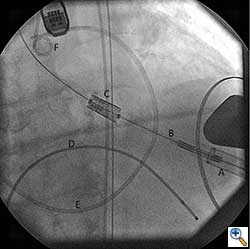

Once optimal C-Arm position has been determined, a small left anterior mini-thoracotomy is made to obtain access to the cardiac apex (Figure 4A, B). Two perpendicular 2-0 prolene pledgeted mattress sutures (or purse string depending on surgeon’s preference) are placed at the apex, taking care not to damage the left anterior descending artery. After the patient is heparinized, the apex is punctured and a guidewire is placed into the left ventricular cavity and advanced through the aortic valve into the aorta under fluoroscopic guidance. Upon confirming position, a 7 French sheath is advanced over the guidewire into the left ventricle and out into the aorta. Using a wire exchange technique under flouroscopy, a stiff guidewire (Lunderquist or Extra-stiff Amplatz) is positioned into the descending thoracic aorta with the aid of a JR4 guide catheter (Boston Scientific Corporation, Massachusetts).

Once the positioning of the valve is confirmed by echocardiography and fluoroscopy, balloon valvuloplasty is performed in a similar fashion to the transfemoral approach described earlier. Upon restoring stable hemodynamics, the mounted Sapien valve on a balloon catheter is introduced transapically and proper position is confirmed by echocardiography and angiography (Figure 4C). For the transapical approach, the recommended position of the prosthesis is 50% of the prosthesis on the aortic side of the aortic annulus and 50% on the ventricular side of the annulus. Since the delivery system is much shorter compared to the transfemoral approach, the direct apical access to the aortic annulus results in less stored torque in the system. Therefore on deployment, the prosthesis does not have the tendency to migrate. During a period of rapid ventricular pacing, the valve is rapidly deployed by expanding the balloon (Figure 5). The valve is not re-ballooned unless there is moderate to severe paravalvular leak. The ventricular sheath is then removed and hemostasis is achieved by tying down the apical purse string sutures during rapid ventricular pacing. Great care must be taken in tying these sutures, as too much tension or torque may cause the ventricular apex to tear and cause uncontrollable bleeding.